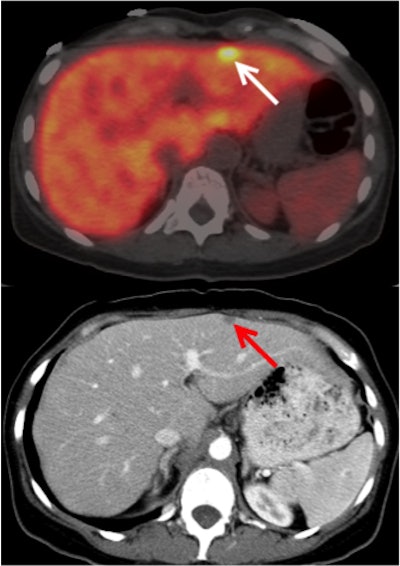

A 49-year-old woman with metastatic pancreatic adenocarcinoma presents with rising CA 19-9 levels. Axial fused PET/CT image with Zr-89 HuMab-5B1 shows focus of uptake in the liver (arrow), correlating with increased liver metastasis seen on diagnostic CT (red arrow) performed two weeks prior. Credit: Christian Lohrmann, Jason Lewis, Wolfgang Weber, Memorial Sloan Kettering Cancer Center; MabVax Therapeutics.PET/CT with Zr-89 DFO HuMab-5B1 led to the detection of very small tumors in the peritoneum and mesenteric lymph nodes that weren't found by CT alone, the researchers found. They concluded that the radiotracer could lead to improvements in the management of pancreatic cancer, including better tumor staging, improved surgical guidance, restaging of metastases, and potential drug selection for therapies that target CA 19-9.